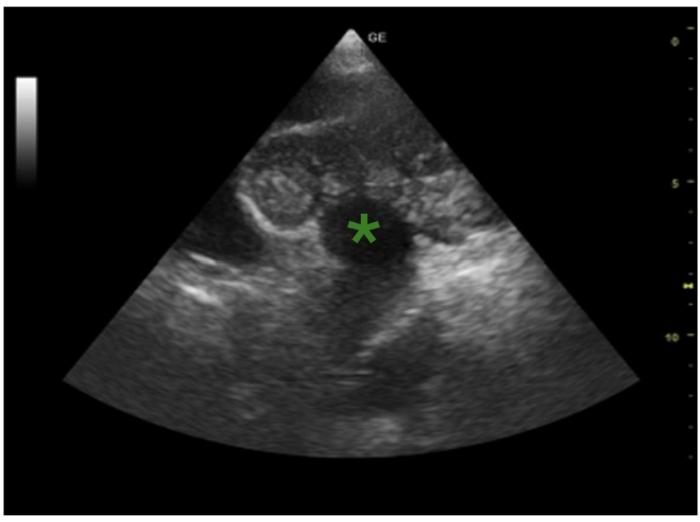

Normalmente, el HSA se localiza en el atrio derecho (AD), tanto en la pared como en la luz; mientras que el quemodectoma suele localizarse en la arteria pulmonar, en la arteria aorta (Figura 1) o en la luz del AD. La localización más frecuente de las lesiones metastásicas es la pared ventricular.

El motivo de consulta es la presencia de una masa cardiaca en el ventrículo derecho, de 3 × 4 cm, identificada hace dos semanas en su veterinario habitual durante el procedimiento diagnóstico de síncopes de resolución espontánea. En el momento de la consulta, la paciente se encuentra en tratamiento con amlodipino (0.1 mg/kg/día), benaceprilo (0.25 mg/kg/12 h) y espironolactona (2 mg/kg/día), pautado por su veterinario habitual.

Durante la exploración física general el único hallazgo relevante es la presencia de un soplo mitral y una frecuencia cardiaca de 140 lpm. La ecocardiografíaconfirma la presencia de una masa en el ventrículo derecho (3.8 × 5 cm) (Figura 2 y 3), junto con insuficiencia mitral en estadio B2 e hipertensión pulmonar (consenso ACVIM). Se instaura terapia con clopidogrel (1.5mg/kg/día), para la prevención de tromboembolismo, y se sustituye el benaceprilo por pimobendan (0.5 mg/kg/12 h).